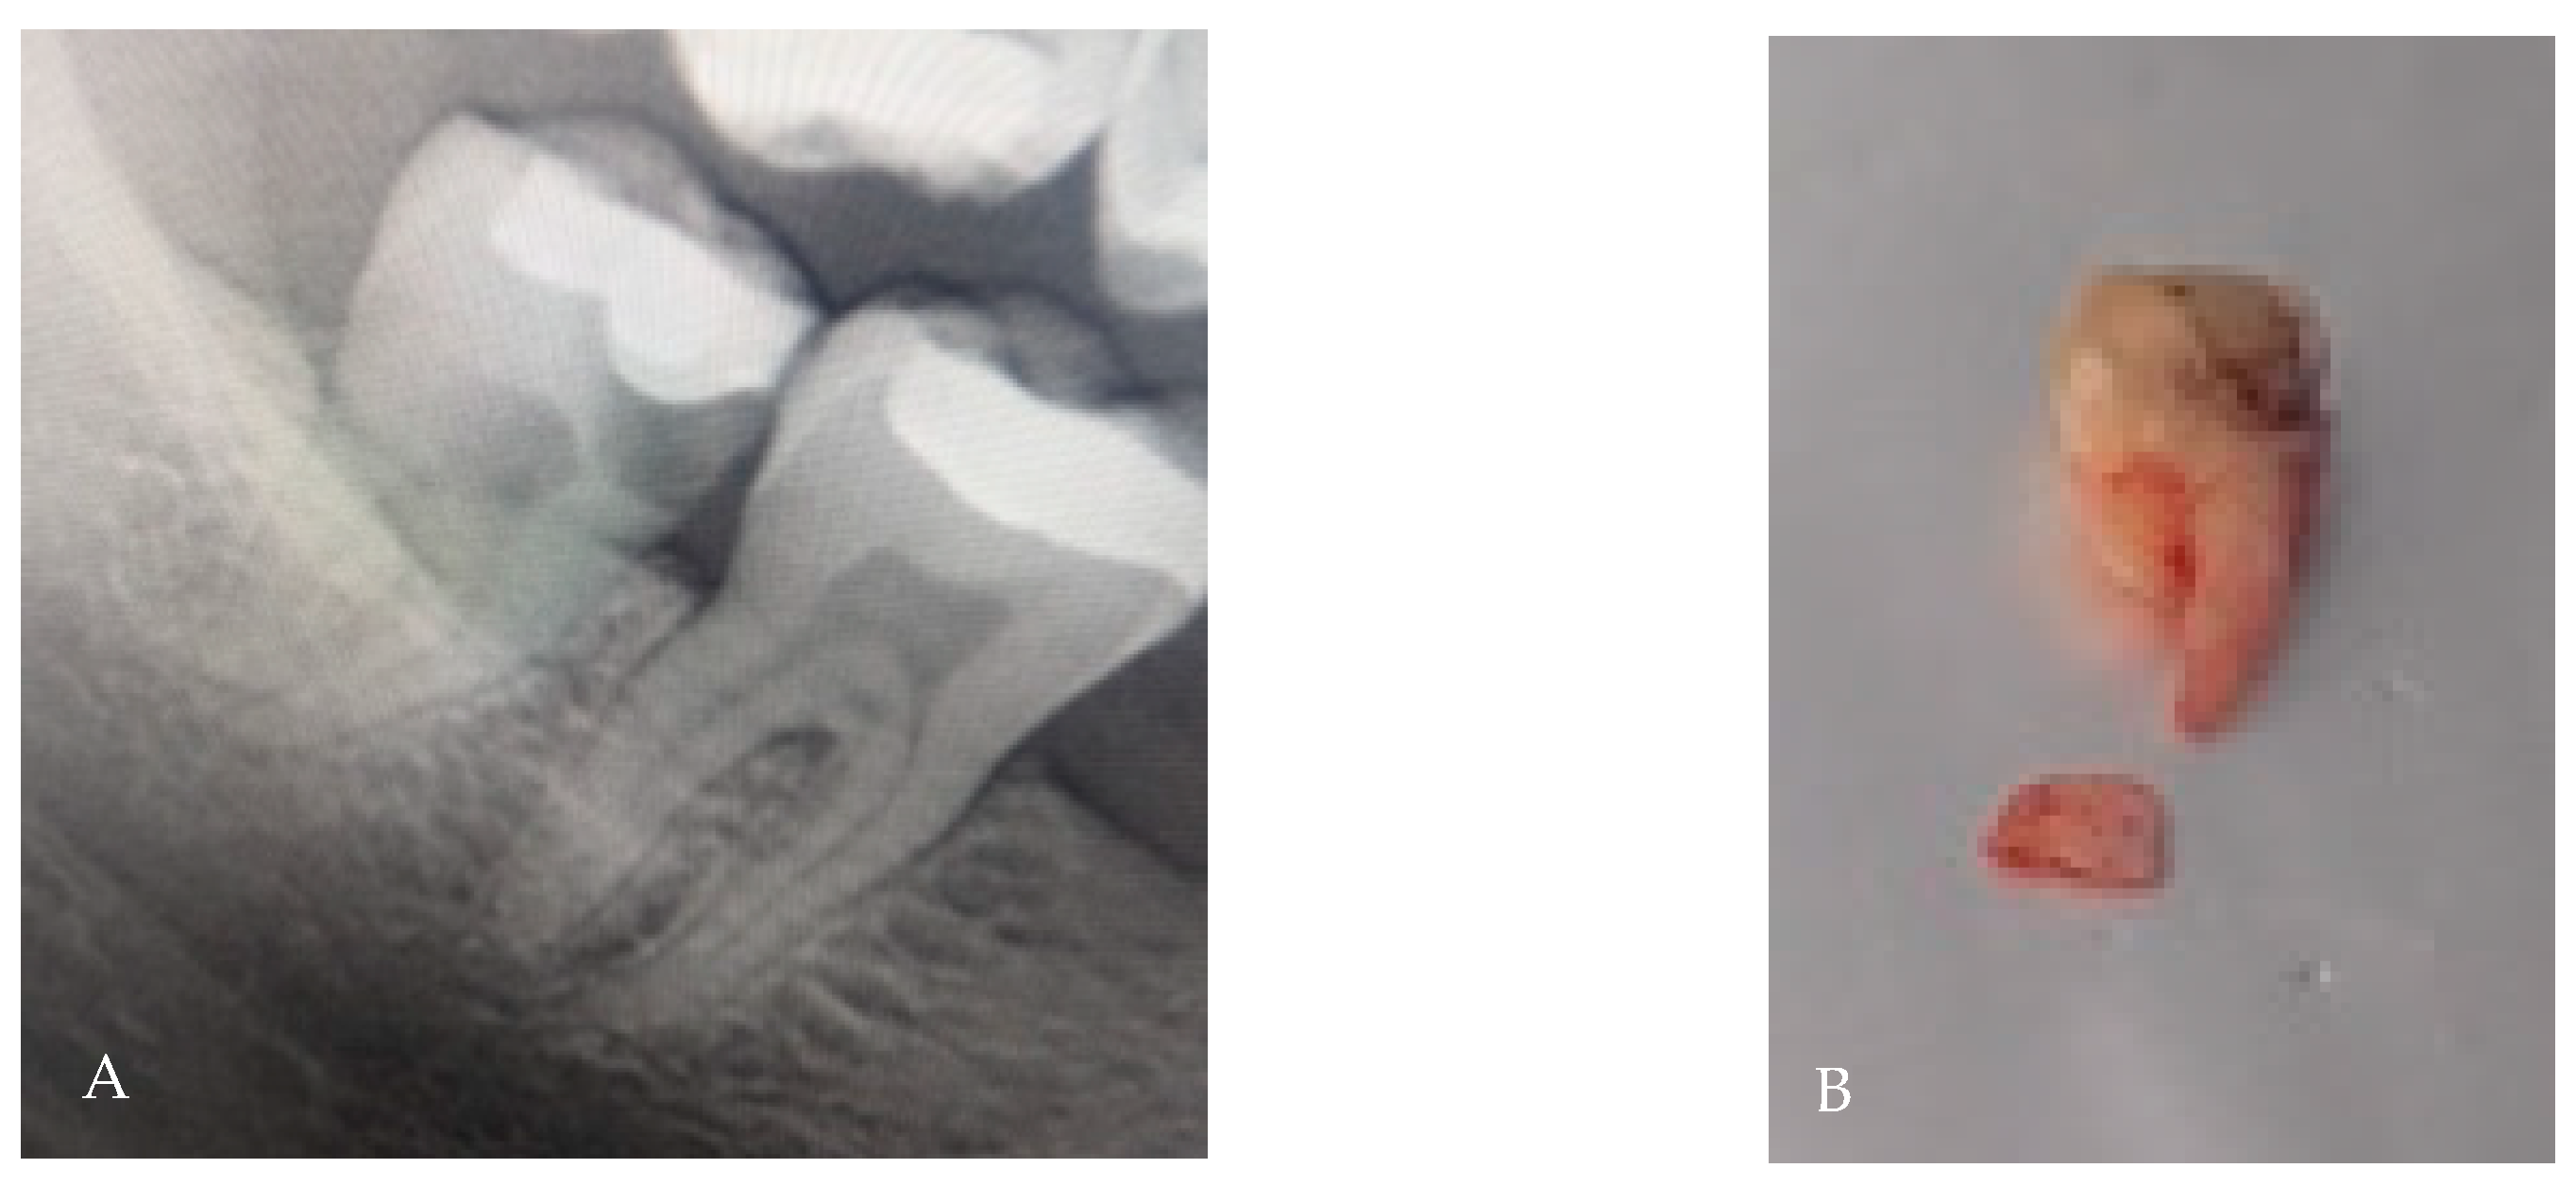

3.7. Dilaceration/Apical Curvature

| Dilaceration | Curved or hooked root apex (>20–40°) | 10–22% | Impedes straight-line removal; risk of apical fracture; may require coronectomy or apex-first approach | [8,9] |

| Dilaceration | 10–22% | Apex-first retrieval; coronectomy if near IAN | [8,9] |